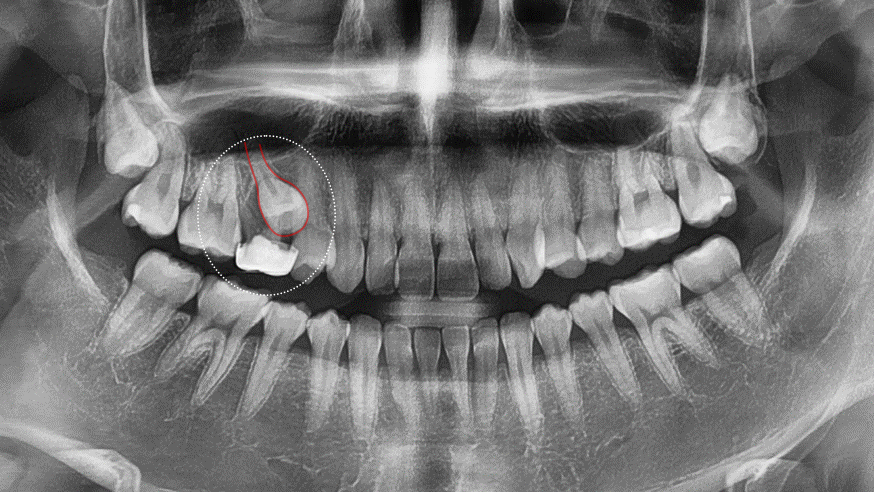

파노라마에서 오른 쪽 위를

자세히보면 유치가 남아있고,

제 2소구치(작은 어금니)가

올라오지 못하는 모습을 볼 수 있습니다.

보통 영구치가 맹출될 때,

유치의 뿌리가 자연스럽게 흡수되며

이로 인해 유치가 흔들리다

빠지는 과정으로 교체됩니다.

그러나 영구치가 제대로 된 방향으로

맹출하지 못하면(이소맹출)

유치의 뿌리를 제대로 녹이지 못하면서

‘유치 만기 잔존’ 증상이 발생하게 됩니다.

유치 발치 후 매복된 영구치(# 15번)를

맹출 유도, 정상적인 배열을 도모하여

개방교합을 개선시키고

정상적인 어금니 교합을 만드는 것을

치료의 목표로 설정하였습니다.